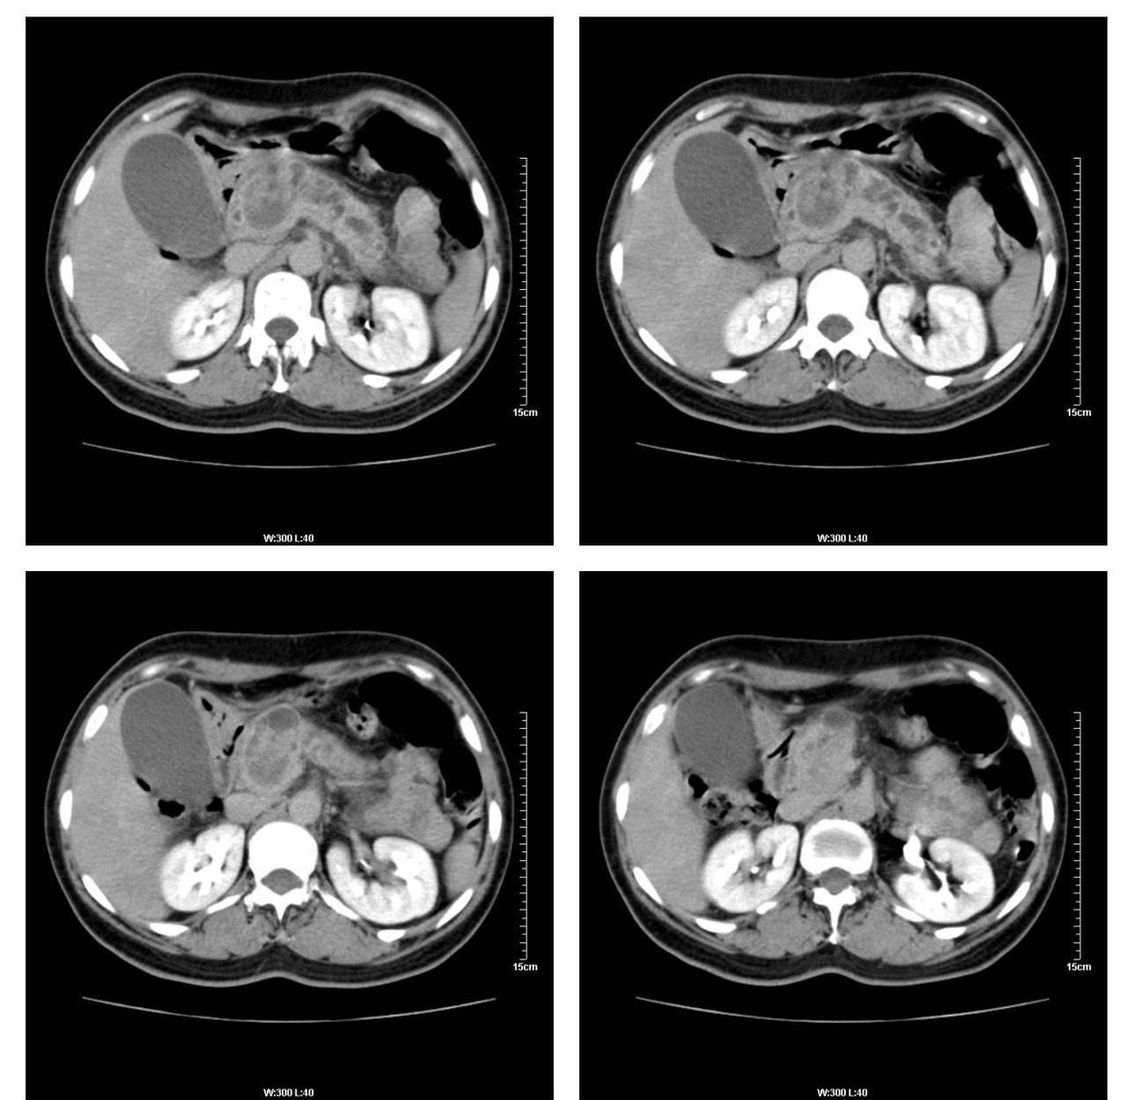

标题: CT13800:女性,52岁。腹痛、腹胀、消瘦及乏力5个月。 [打印本页]

标题: CT13800:女性,52岁。腹痛、腹胀、消瘦及乏力5个月。

慢性胰腺炎、胰腺假囊肿形成,胆总管梗阻,胆囊扩张

胰腺癌可能大

考虑胰头癌

考虑胰腺囊腺癌。

考虑胰头癌可能。

各期时间抓的不太好,门静脉始终显示不佳(门脉瘤栓形成?)。